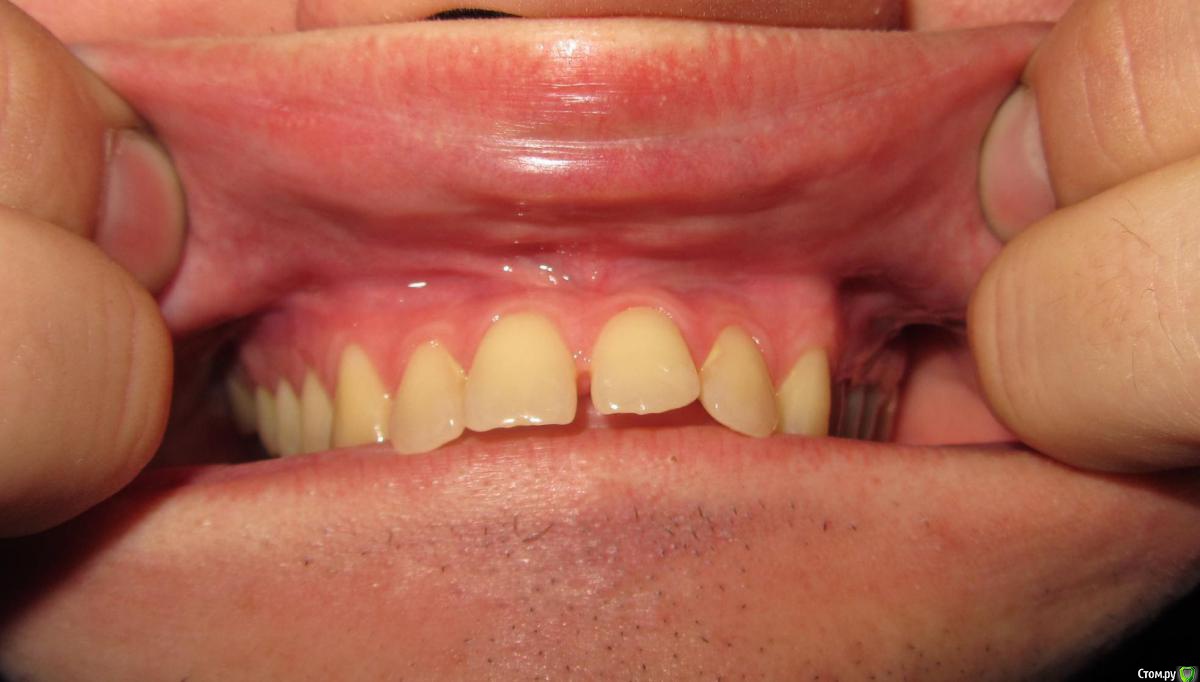

janis1 Опубликовано 14 ноября, 2015 Поделиться Опубликовано 14 ноября, 2015 Доброго времени суток, уважаемые профессионалы.Очень надеюсь на вашу помощь.Коротко о себе:37 лет, пол мужской. Так сложилось что в последнее время меня постигло сразу три проблемы,как мне кажется все они имеют между собой четкую связь. Основная проблема, с болями верхней челюсти, началась у меня около месяца назад. Боль не очень сильная, но практически постоянная. Боль не имеет какой-либо конкретной локации (болит именно вся челюсть). С утра она меньше, ближе к вечеру усиливается. В последнее время немного отдаёт в скулу. Одновременно с появлением боли, во рту, в районе дёсен, появился как бы привкус соды (немного похожий на вкус крови, но крови в ротовой полости нет).И в довершение всего начали катастрофически искривляются зубы верхней челюсти.На самом деле проблемы с прикусом у меня были уже с детства, примерно в 10 - 12 лет я носил пластинку для исправления прикуса.Но к сожалению лечение так и не закончил, соответственно прикус все это время у меня был неправильным, но до последнего времени он меня не беспокоил, так как был если так можно сказать "в пределах разумного", и в течении долгого времени был неизменен, но в последние несколько месяцев верхние зубы искривились настолько катастрофически что что я реально начал шепелявить. При попытке расшатывания зубы стоят крепко, не болтаются. Пока во всяком случае... Со всеми этими проблемами я пробовал обращаться к зубному хирургу и ортодонту,ни хирург, ни ортодонт к которым я обращался не смогли назвать каких-либо конкретных причин по которым может появляться боль в верхней челюсти и привкус во рту.Врачи к которям я обращался действительно хорошие специалисты, но похоже видят проблемы узко по своей специализации.Единственно хирург указал на то, что возможно придется удалять восьмерки, а ортодонт предложил установить брекеты на обе челюсти.Я прекрасно понимаю что с таким прикусом мне действительно не избежать установки брекетов, но меня беспокоит то, что не найдена причина происхождения всех проблем о которых я написал. Очень надеюсь на вашу помощь в поиске возможных причин проявления моих проблем. Заранее благодарен! Ссылка на комментарий

Jurai Опубликовано 22 ноября, 2015 Поделиться Опубликовано 22 ноября, 2015 Есть проблема во фронтальном участке верхней челюсти: общая убыль костной ткани, ячеистая структура кости. смещение зубов так, что корни изогнулись, это значит, что либо резорбция (рассасывание) либо очень длительное уже идет воздействие. Могу подозревать новооборазование в этом участке.Вам нужна консультация челюстно-лицевого хирурга-онколога. 1 Ссылка на комментарий